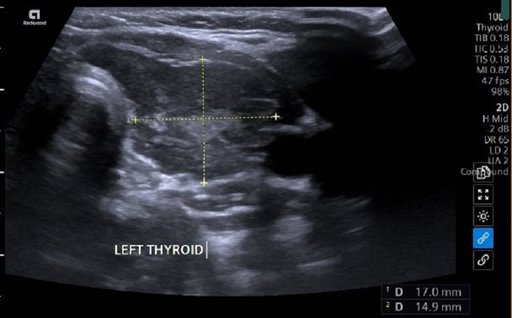

- Siêu âm;